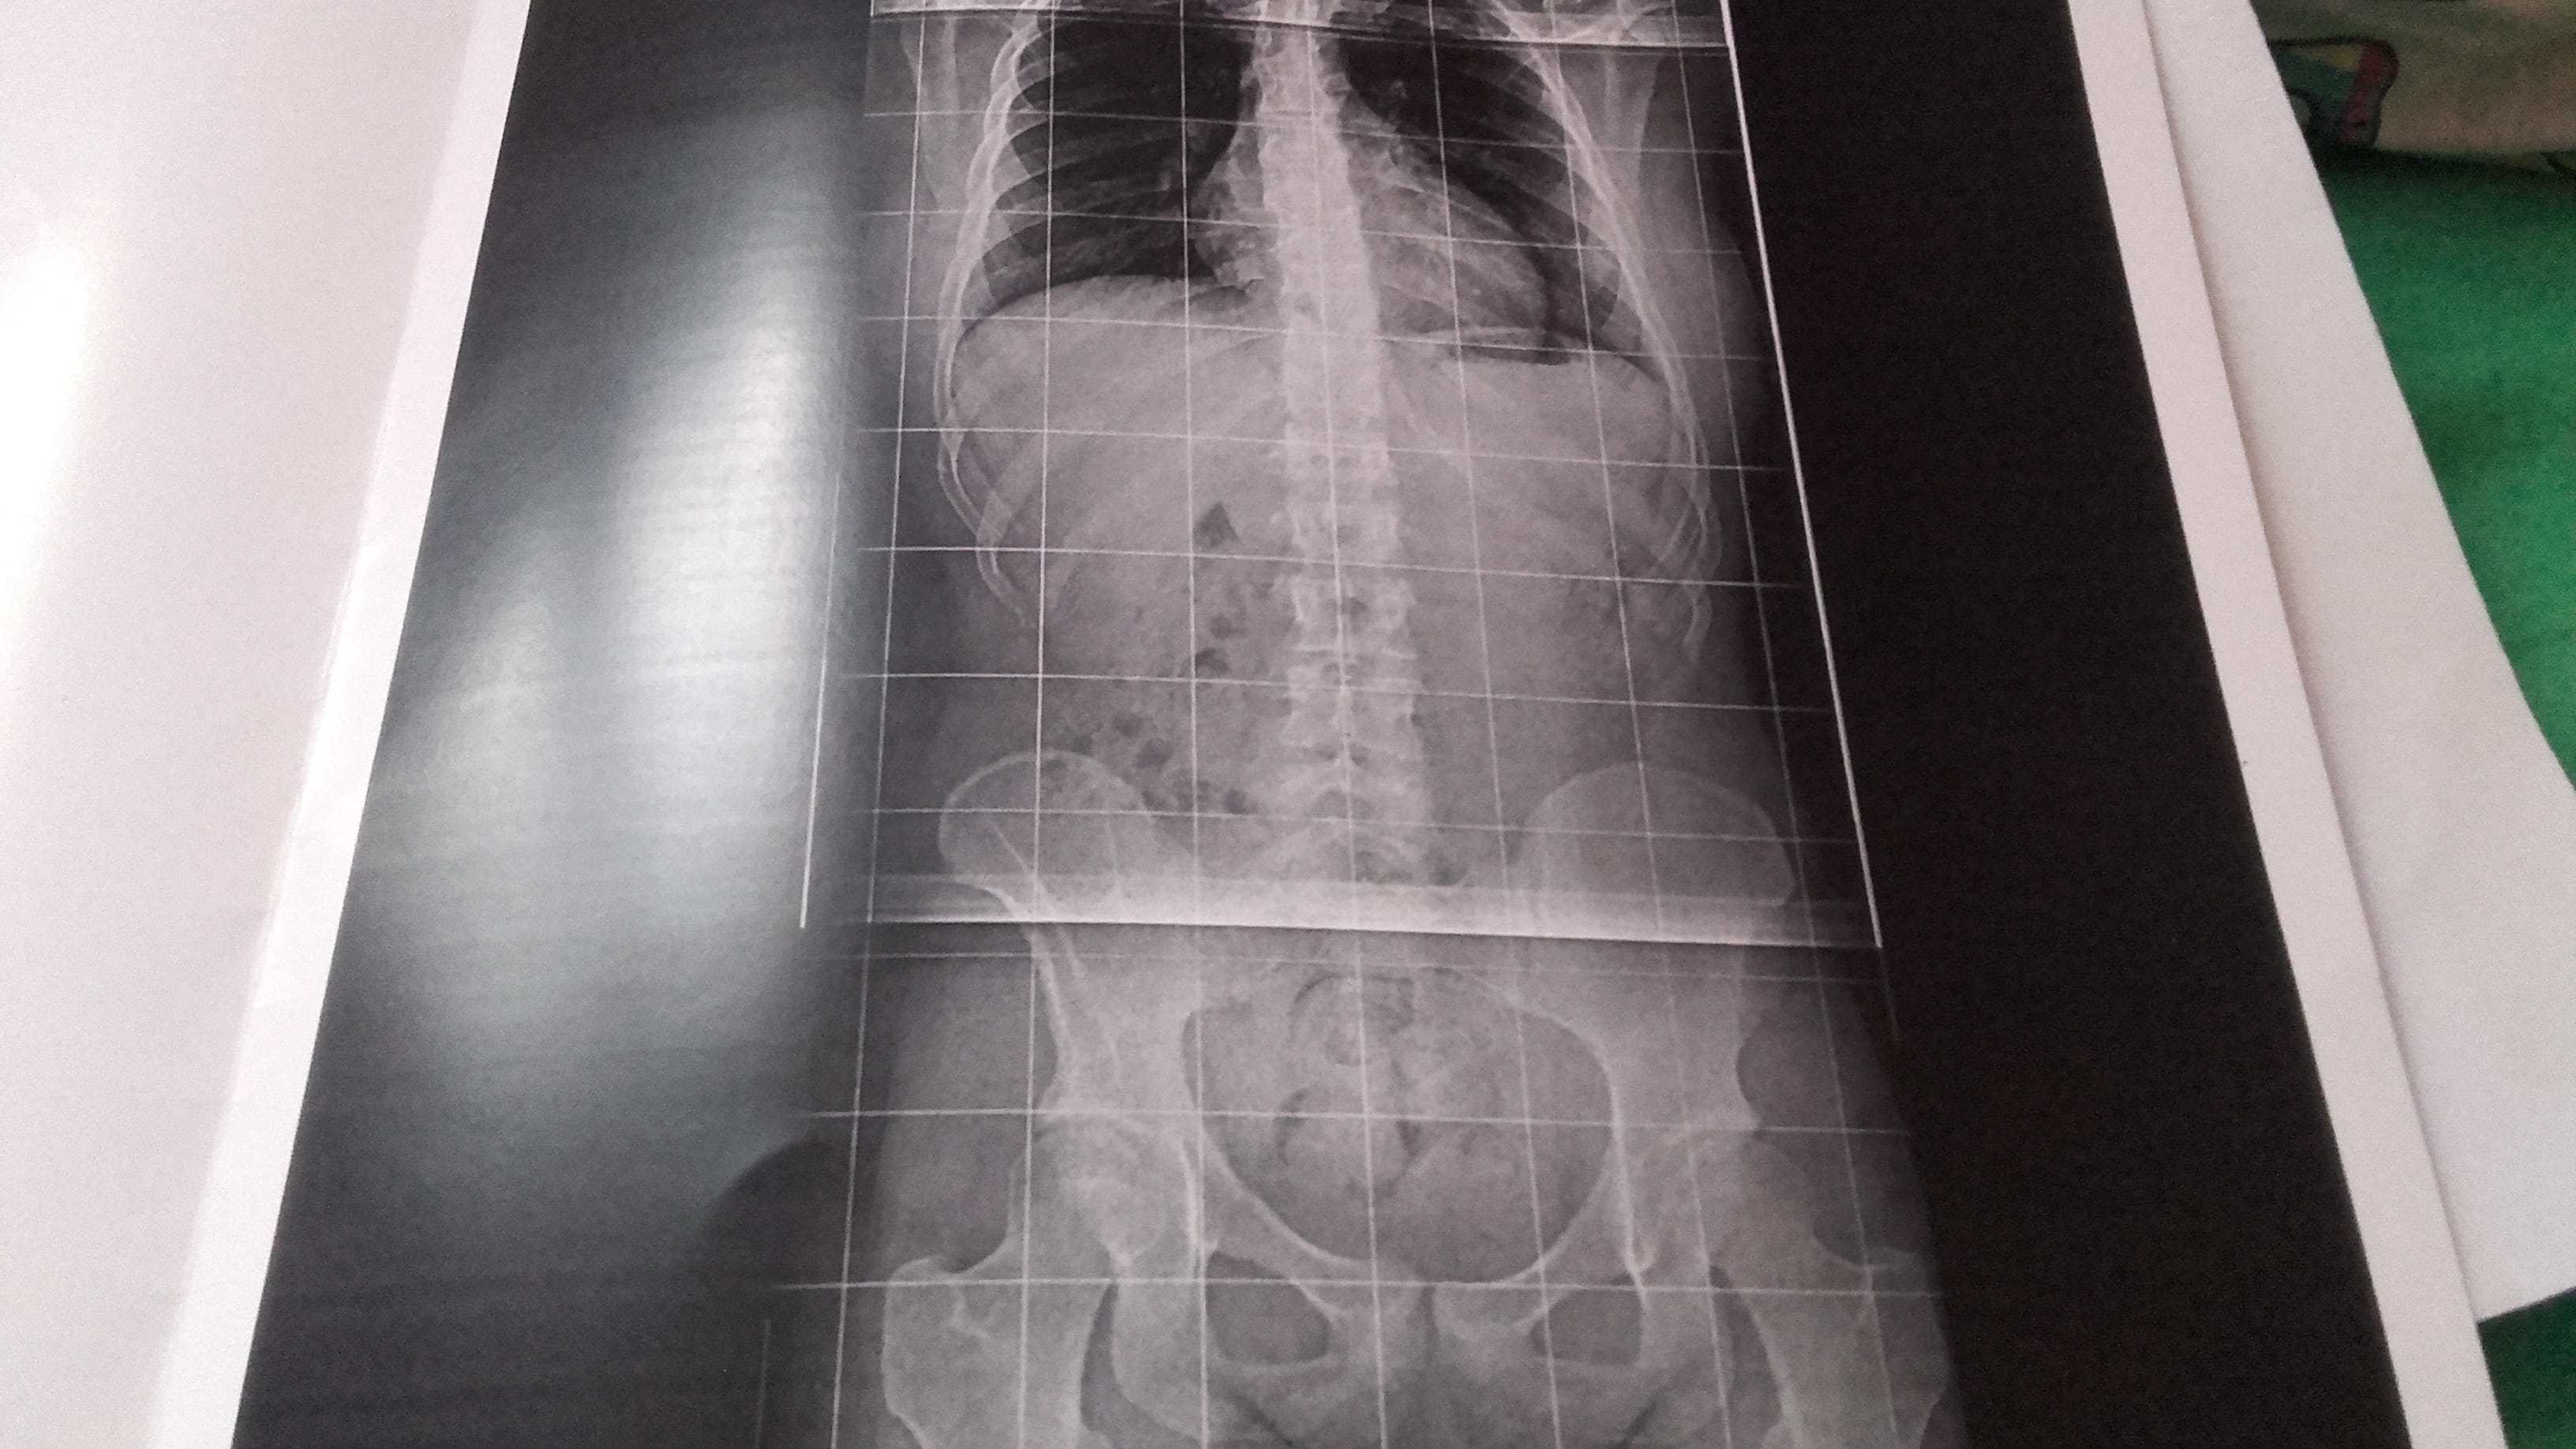

j ai fais une radio de la colonne mais rien est ce possible que ce soit un décalage du bassin mais j ai peur que mon médecin ne me croit pas.

je vous mets

la photo de la radio on voit une partie du bassin.